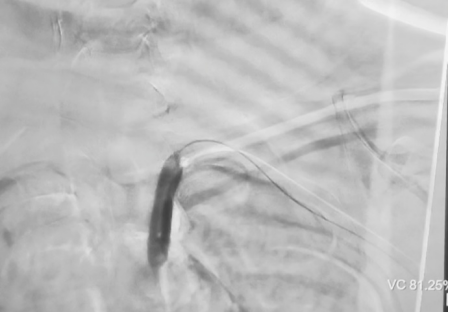

球囊预扩,打开通道:

wuwei